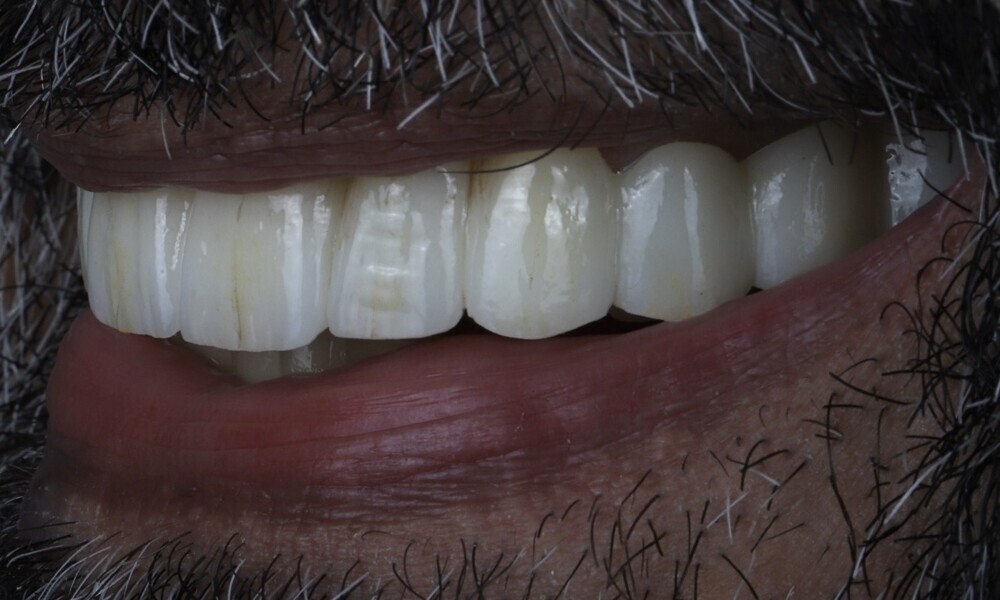

The delivery of the final prosthesis was then performed, and the aesthetics, occlusion and function were verified (Figs. 51–55). The panoramic control radiograph showed that all measurements were within expected ranges (Fig. 56).

At the 18-month follow-up after completing the treatment, an intra-oral, extra-oral and radiographic evaluation were performed. No pathologies were observed, and the results remained stable over time (Figs. 57–62). The patient expressed his satisfaction with the treatment outcomes, stating, “Seeing my new smile before starting the procedure was a game-changer. I was confident from the beginning that my final result would be as I had imagined.”

The combination of Straumann BLX implants with the Straumann RevEX scan bodies for a full monolithic design and integrated into a comprehensive Smilecloud digital workflow yielded favourable treatment outcomes for full-arch rehabilitation in this case. The seamless coordination between the surgical and prosthetic phases, facilitated by state-of-the-art digital technologies, enhanced precision, efficiency, and patient comfort and satisfaction. This case underscores the important role of digital dentistry in ensuring reliable and aesthetically satisfying results in implant therapy.